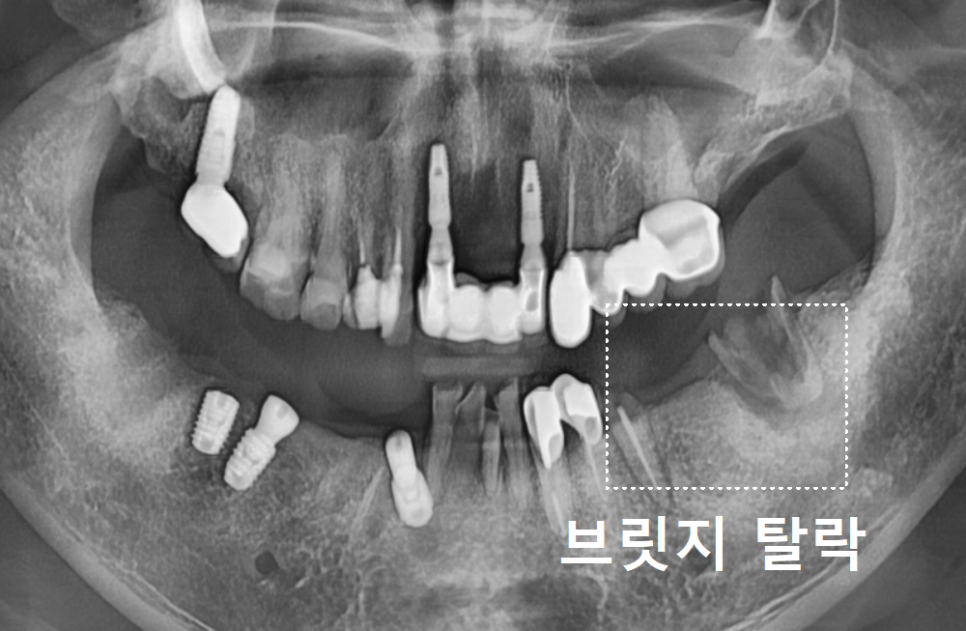

이 환자분은 오른쪽 아래,

무려 5개의 치아를 연결한

긴 브릿지가 통째로 빠져서 오셨는데요.

250507

250610

설상가상이라 했던가요.

반대편인 왼쪽 어금니 브릿지(#35~37)마저

탈락해버렸어요.